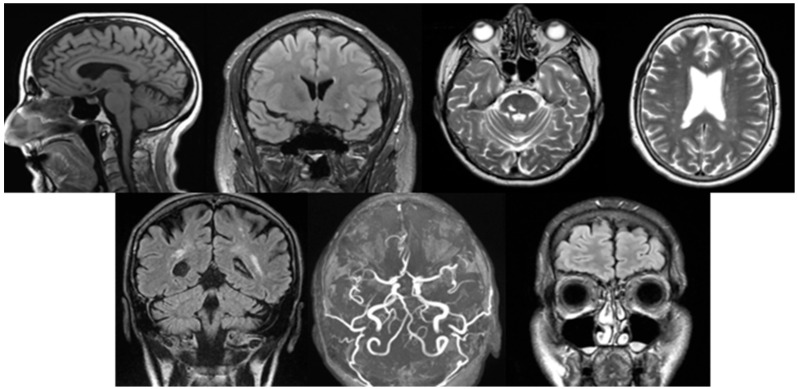

Background/Objectives: Dizziness is a frequent medical complaint with neurological, otolaryngological, and psychological origins. Imaging studies such as CT (Computer Tomography), cervical X-rays, and ultrasound aid diagnosis, while MRI (Magnetic Resonance Imaging) is crucial for detecting brain abnormalities. Our purpose is to identify structural brain changes associated with vertigo, assess pre-MRI diagnostic approaches, and evaluate treatment strategies. Methods: A case-control study of 232 vertigo patients and 232 controls analyzed MRI findings, pre-MRI examinations, symptoms, and treatments. Statistical comparisons were performed using chi-square and t-tests (p < 0.05). Results: White matter lesions, lacunar infarcts, Circle of Willis variations, and sinusitis were significantly more frequent in vertigo patients (p < 0.05). Pre-MRI diagnostics frequently identified atherosclerosis (ultrasound) and spondylosis (X-ray). Common symptoms included headache, imbalance, and visual disturbances. The most frequent post-MRI diagnosis was Benign Paroxysmal Positional Vertigo (BPPV). Treatments included lifestyle modifications, physical therapy (e.g., Epley maneuver), and pharmacological therapies such as betahistine. Conclusions: MRI revealed structural brain changes linked to vertigo. Pre-MRI assessments are essential for ruling out vascular and musculoskeletal causes. A multidisciplinary treatment approach is recommended. Trial Registration: This study was registered in ClinicalTrials.gov with the trial registration number NCT06848712 on 22 February 2025.

Abstract Image